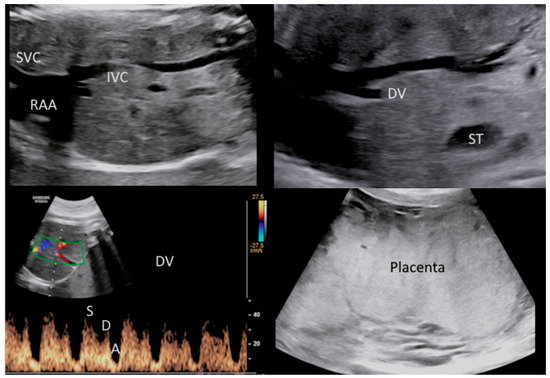

2. The Case

- Lucas, M.J.; Theriot, S.K.; Wendel, G.D., Jr. Doppler systolic-diastolic ratios in pregnancies complicated by syphilis. Obstet. Gynecol. 1991, 77, 217–222. [Google Scholar] [CrossRef] [PubMed]

- Rac, M.W.F.; Bryant, S.N.; McIntire, D.D.; Cantey, J.B.; Twickler, D.M.; Wendel, G.D., Jr.; Sheffield, J.S. Progression of ultrasound findings of fetal syphilis after maternal treatment. Am. J. Obstet. Gynecol. 2014, 211, 426.e1–426.e6. [Google Scholar] [CrossRef]